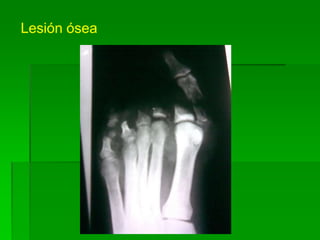

Lesión ósea

Lesiones de pie

Fractura 1ª falange de quinto dedo izquierdo

Fractura de primera falange

de quinto dedo